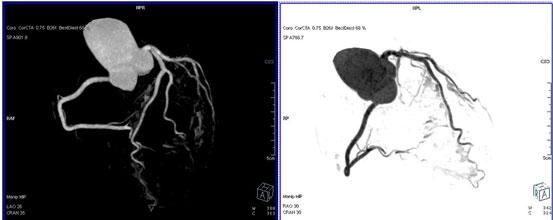

64排螺旋CT冠狀動脈血管成像:

1、簡單:無需經動脈插管,隻需象平時靜脈輸液一樣在肘靜脈内推注相對适量對比劑,然後行快速掃描即可完成整個檢查。

2、安全:64排螺旋CT冠狀動脈造影,對比劑用量較少,無需動脈插入導管,患者無需承擔麻醉及動脈插管等帶來并發症的危險。在冠狀動脈血管疾病的篩查、早期診斷、冠狀動脈成形術和搭橋術前、術後血管評價,冠狀動脈起源異常及心肌橋等方面極具優勢。

3、後處理功能豐富:西門子公司爲SOMATOM Definition AS+ 128層4D螺旋CT配備了功能強大的後處理工作站:MMWP(多産品工作站)和最新型的醫學影像IT工作平台,Syngo.via,智能,便捷。